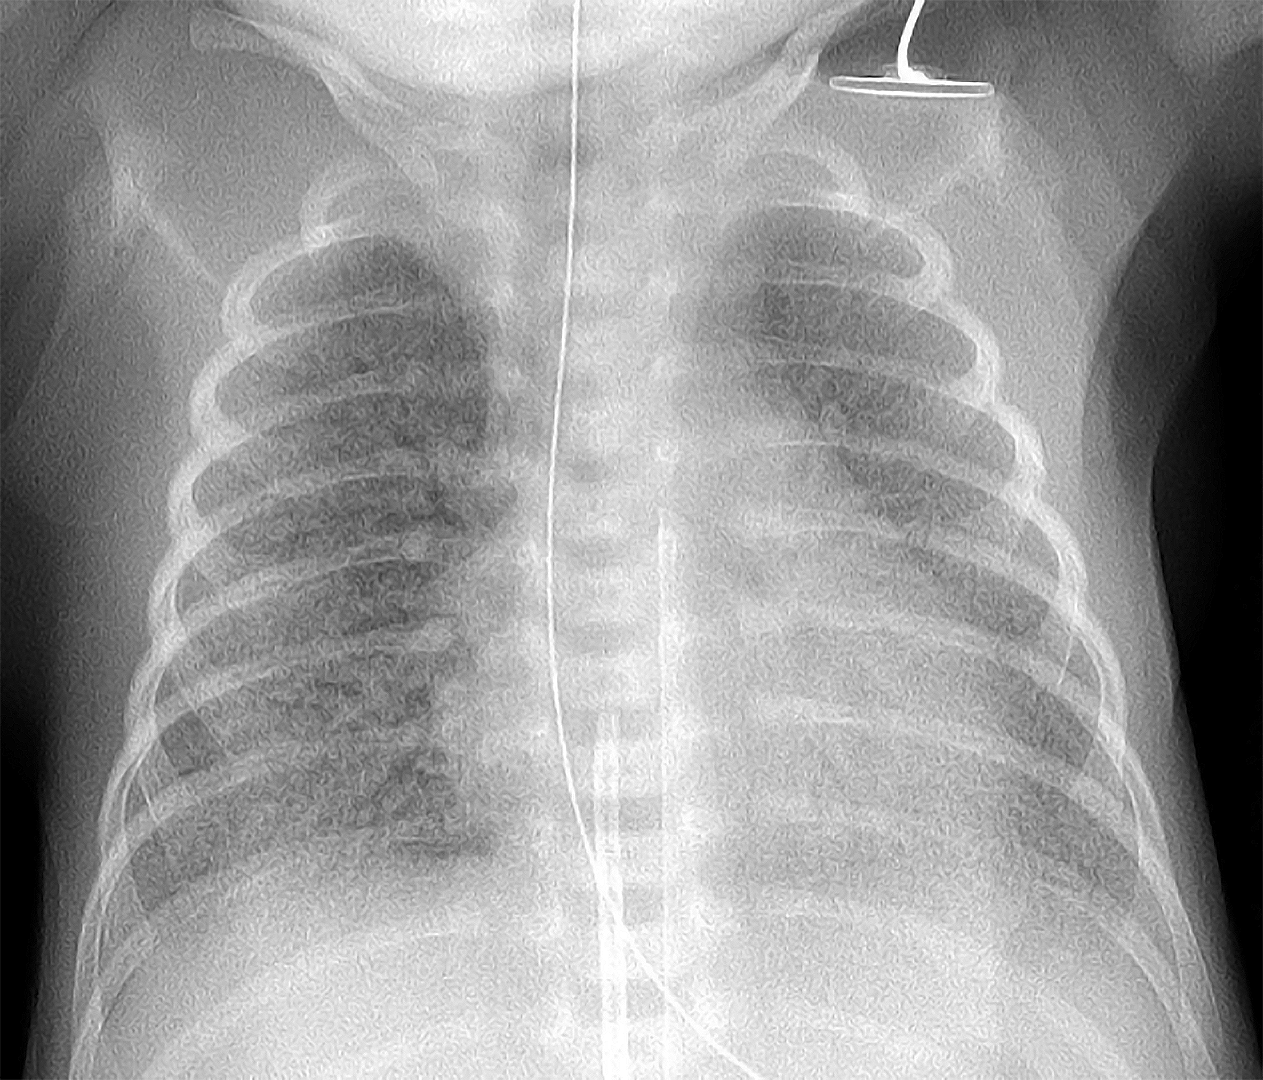

Chest Xray showing acute respiratory distress syndrome. Download Chest X Ray Findings In Respiratory Distress Syndrome Findings of ards — ards should be suspected in patients with progressive symptoms of dyspnea, an increasing requirement for. For almost 20 years, the evaluation of the extension and distribution of lung opacities in ards patients had been. Respiratory distress syndrome (rds) is the leading cause of death in babies who are born. In berlin definition 2012 [2], the most. Chest X Ray Findings In Respiratory Distress Syndrome.

Initial Xray chest respiratory distress syndrome grade 1°. One hour Chest X Ray Findings In Respiratory Distress Syndrome Respiratory distress syndrome (rds) is the leading cause of death in babies who are born. Findings of ards — ards should be suspected in patients with progressive symptoms of dyspnea, an increasing requirement for. In berlin definition 2012 [2], the most recognized version up to now, the disease was defined as a syndrome that onset within one. In patients with. Chest X Ray Findings In Respiratory Distress Syndrome.